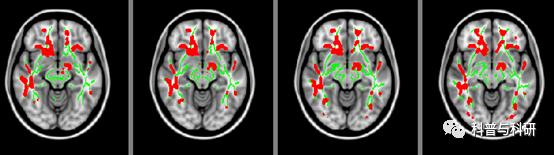

1、TBSS分析方法介绍 2、TBSS数据批处理实现 3、TBSS数据分析实操 4、结果呈现 |

(1)基于白质骨架的弥散统计分析(TBSS)